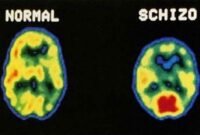

5 Penyakit yang Penderitanya Harus Minum Obat Seumur Hidup

sepanjang hidup. 1. Hipertensi Yaitu suatu kekuatan yang mendorong darah ke dinding bagian dalam arteri. Dampak dari hipertensi dapat meningkatkan …selangkapnya